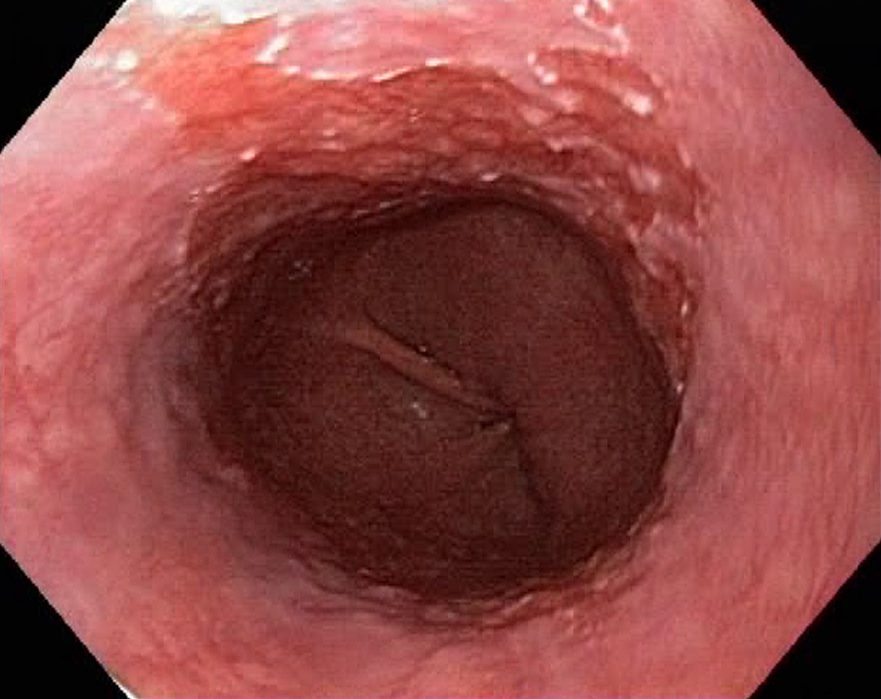

Barrets Oesophagus (NBI, Narrow Band Imaging)